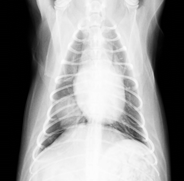

術後は良好に経過し、手術後6日目に退院されました。病理検査にて肺乳頭状腺癌との診断でした。現在は他の肺に転移しないように抗がん治療を受けていますが、元気いっぱいで過ごしています。いつまでも元気で長生きしてほしいですね(^0^)